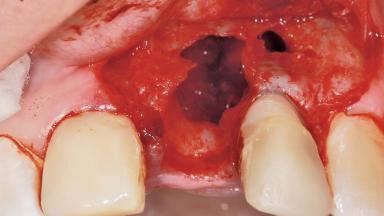

Bone Augmentation Horizontal|Staged

Augmentation Materials Xenogenous|Membrane

Bone Volume Deficient horizontally, requiring prior grafting